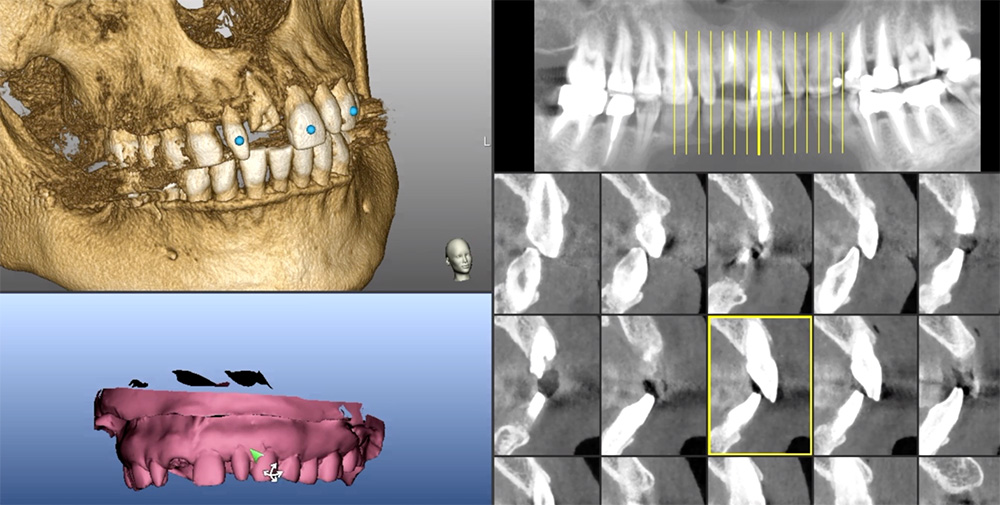

Implant dentistry demands precision placement of the fixture. Ideal location and position, dimension (length and diameter) and depth and angulation are mandated for positive treatment outcomes. Restoratively driven implant placement is paramount for the overall integrity of the dentition. Thus, it is essential to first visualize the final prosthesis in place in order to determine the type and number of implants necessary to support the intended prosthesis based on residual bone volume [Figures 1a, 1b].

Figure 1a

Figure 1b